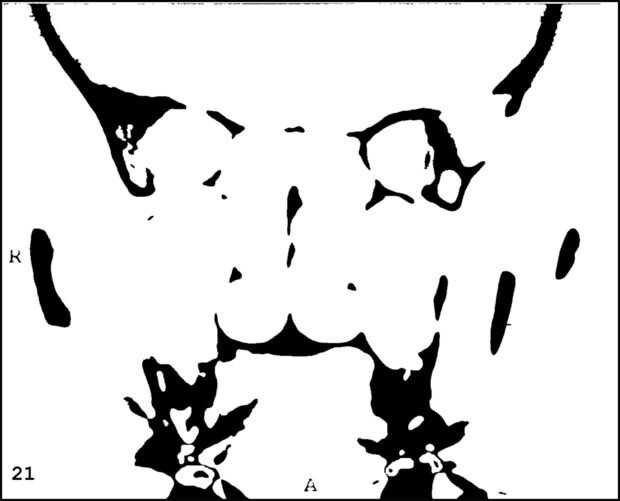

¡ Wow! Este fue por menos de 12 horas y tengo 1.000 visitas! Esto es sólo mi segundo instructable, así que estoy encantada. Decidí seguir adelante y publicar las imágenes que utiliza. Se trata de MRI de mi esposa, así que ella sólo puede tener lo mundos primer código abierto jefe. Mi lámpara utiliza solamente las primeras 16 capas, pero te di todos 34 que representa. Seguir adelante y usar estas imágenes, pero si lo haces, por favor me manden una imagen de lo que te ocurrió así que puedo hacerla sentir un poco famoso. ¡Que te diviertas!